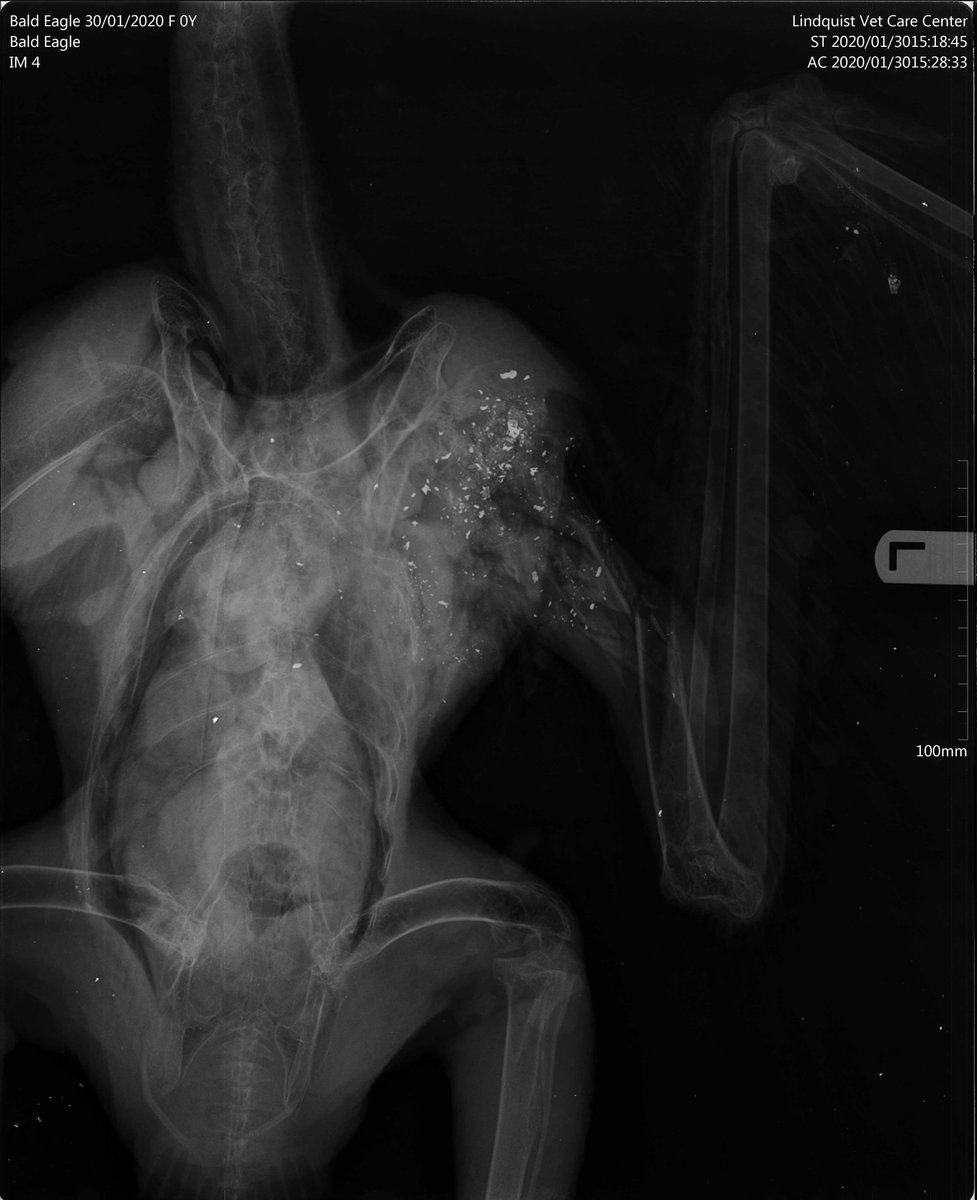

Conservation agents need help to find who shot and killed a bald eagle one mile south of Adair along Oak Grove Way. Bullet fragments are evident in the X-rays. Call Adair County Agent Kevin Powell at (660) 216-1389 with info or Operation Game Thief at 1-800-392-1111.pic.twitter.com/jDqnhjfzTB